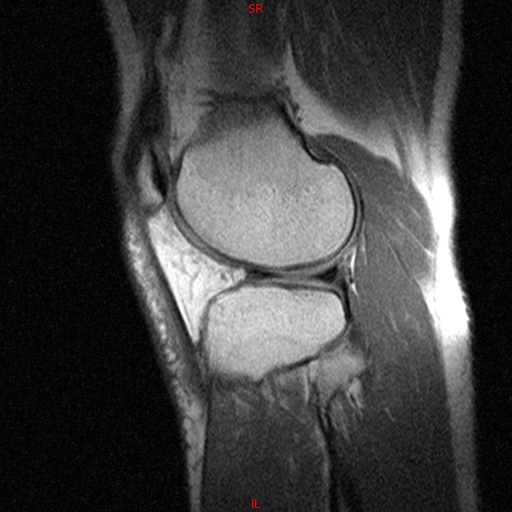

• Resonancia PATOLÓGICA MENISCOPATIA INTERNA DP SAGITAL

• Resonancia NORMAL RODILLA SAG DENSIDAD PROTONICA

• Resonancia NORMAL RODILLA SAG T1

• Resonancia PATOLÓGICA EDEMA OSEO Y DERRAME ARTICULAR